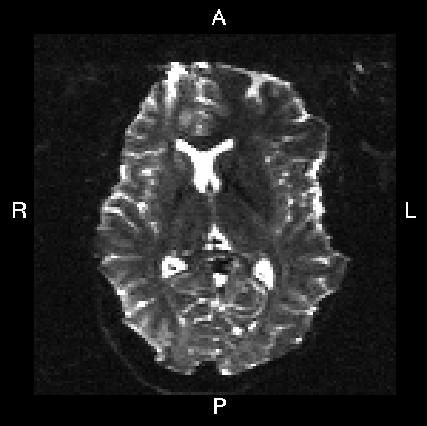

Below you see four examples of images acquired with different phase encoding. Below the images you see what you would find in the PDF protocol generated on a Siemens scanner for these acquisitions. Unfortunately I don't have enough experience of other scanner manufacturers to know where to find the information from those.

If you are uncertain about how to create your own --acqp file I suggest you get your scanner protocol, load your images into FSLVIEW and then find which of the images below that looks most like then one you have. When you have done that compare the "Phase enc." entry below that image with that in your protocol. When you are happy that you have found the right column you can use the three first values from the vector below the image.

| What you see in FSLeyes |

|---|---|---|---|---|

Phase enc. dir L >> R Echo spacing 0.96 ms EPI factor 128 |

| In --acqp file | 0 1 0 0.095 | 0 -1 0 0.095 | 1 0 0 0.122 | -1 0 0 0.122 |